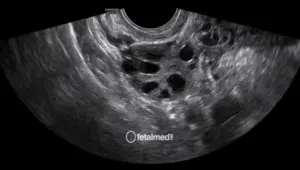

O perfil biofísico fetal (PBF) é um exame que avalia o bem-estar do bebê através da observação de parâmetros biofísicos por ultrassonografia. Ele combina a avaliação de movimentos fetais, tônus muscular, movimentos respiratórios e volume de líquido amniótico.

Cada parâmetro recebe uma pontuação, e o resultado final indica se o bebê está bem ou se precisa de acompanhamento mais intensivo.